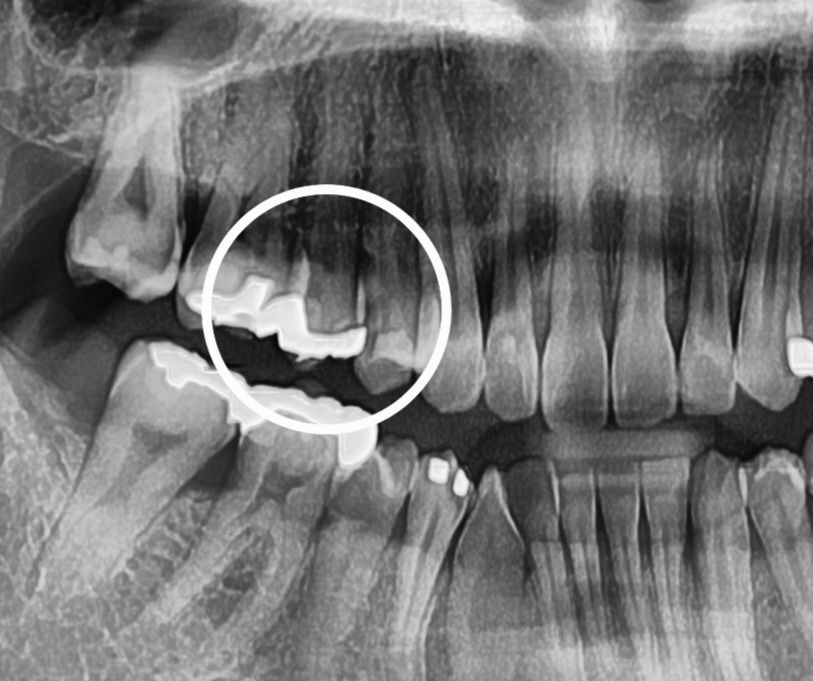

15번치아가 찬물을 마시면 5초동안 아픕니다

치주 2군데 가봤는데 한군데는 이상 없으니 일주일정도 기다려보라고 하시고 한군데는 금간것으로 보이며 신경치료후 크라운해야될거같다고 하시는데 사진보고 조언해주실분 계신가요ㅠ 가만히 있을때는 괜찮습니다 밥먹을때도 괜찮아요

사진상으로는 원인이 명확히 보이진 않습니다.

증상이 계속되면 기존수복물을 제거해봐야 합니다

예전에 치료를 햇던 부위가 충치가 심햇던거 같습니다. 치료햇던 하방으로 방사선 투과상이 보이기도 하니 계속 불편하시면 신경치료를 하셔야될것같습니다.